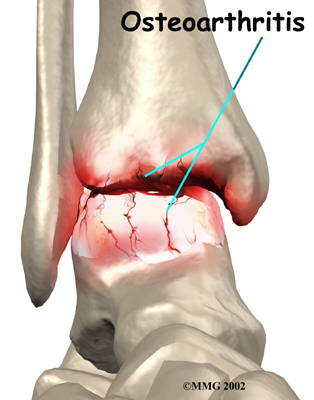

Injury to a joint, such as a bad sprain or fracture, can cause damage to the articular cartilage. The cartilage can be bruised when too much pressure is exerted on it. This damages the cartilage, although if you look at the surface it may not appear to be any different. The injury to the material doesn't show up until months later. Sometimes the cartilage surface is damaged even more severely, and pieces of the cartilage are ripped from the bone. These pieces do not heal back and usually must be removed from the joint surgically. If not, they may float around in the joint, causing the joint to catch and be painful. These fragments of cartilage may also do more damage to the joint surface.

Once this cartilage is ripped away, it does not normally grow back. Unlike bone, holes in the surface are not simply replaced by the cartilage tissue around the hole. Instead the defects are filled with scar tissue. The scar tissue that forms is not nearly as good a material for covering joint surfaces as the cartilage it replaces. It just can't support weight and isn't smooth like true articular cartilage.

An injury to a joint, even if it does not injure the articular cartilage directly, can alter how the joint works. This is true for a fracture where the bone fragments heal differently from the way they were before the break occurred. It is also true when ligaments are damaged that lead to instability in the joint. When an injury results in a change in the way the joint moves, the injury may increase the forces on the articular cartilage. This is similar to any mechanical device or machinery. If the mechanism is out of balance, it wears out faster.

Over many years this imbalance in the joint mechanics can lead to damage to the articular surface. Since articular cartilage cannot heal itself very well, the damage adds up. Finally, the joint is no longer able to compensate for the increasing damage, and it begins to hurt. The damage occurs well before the pain begins.